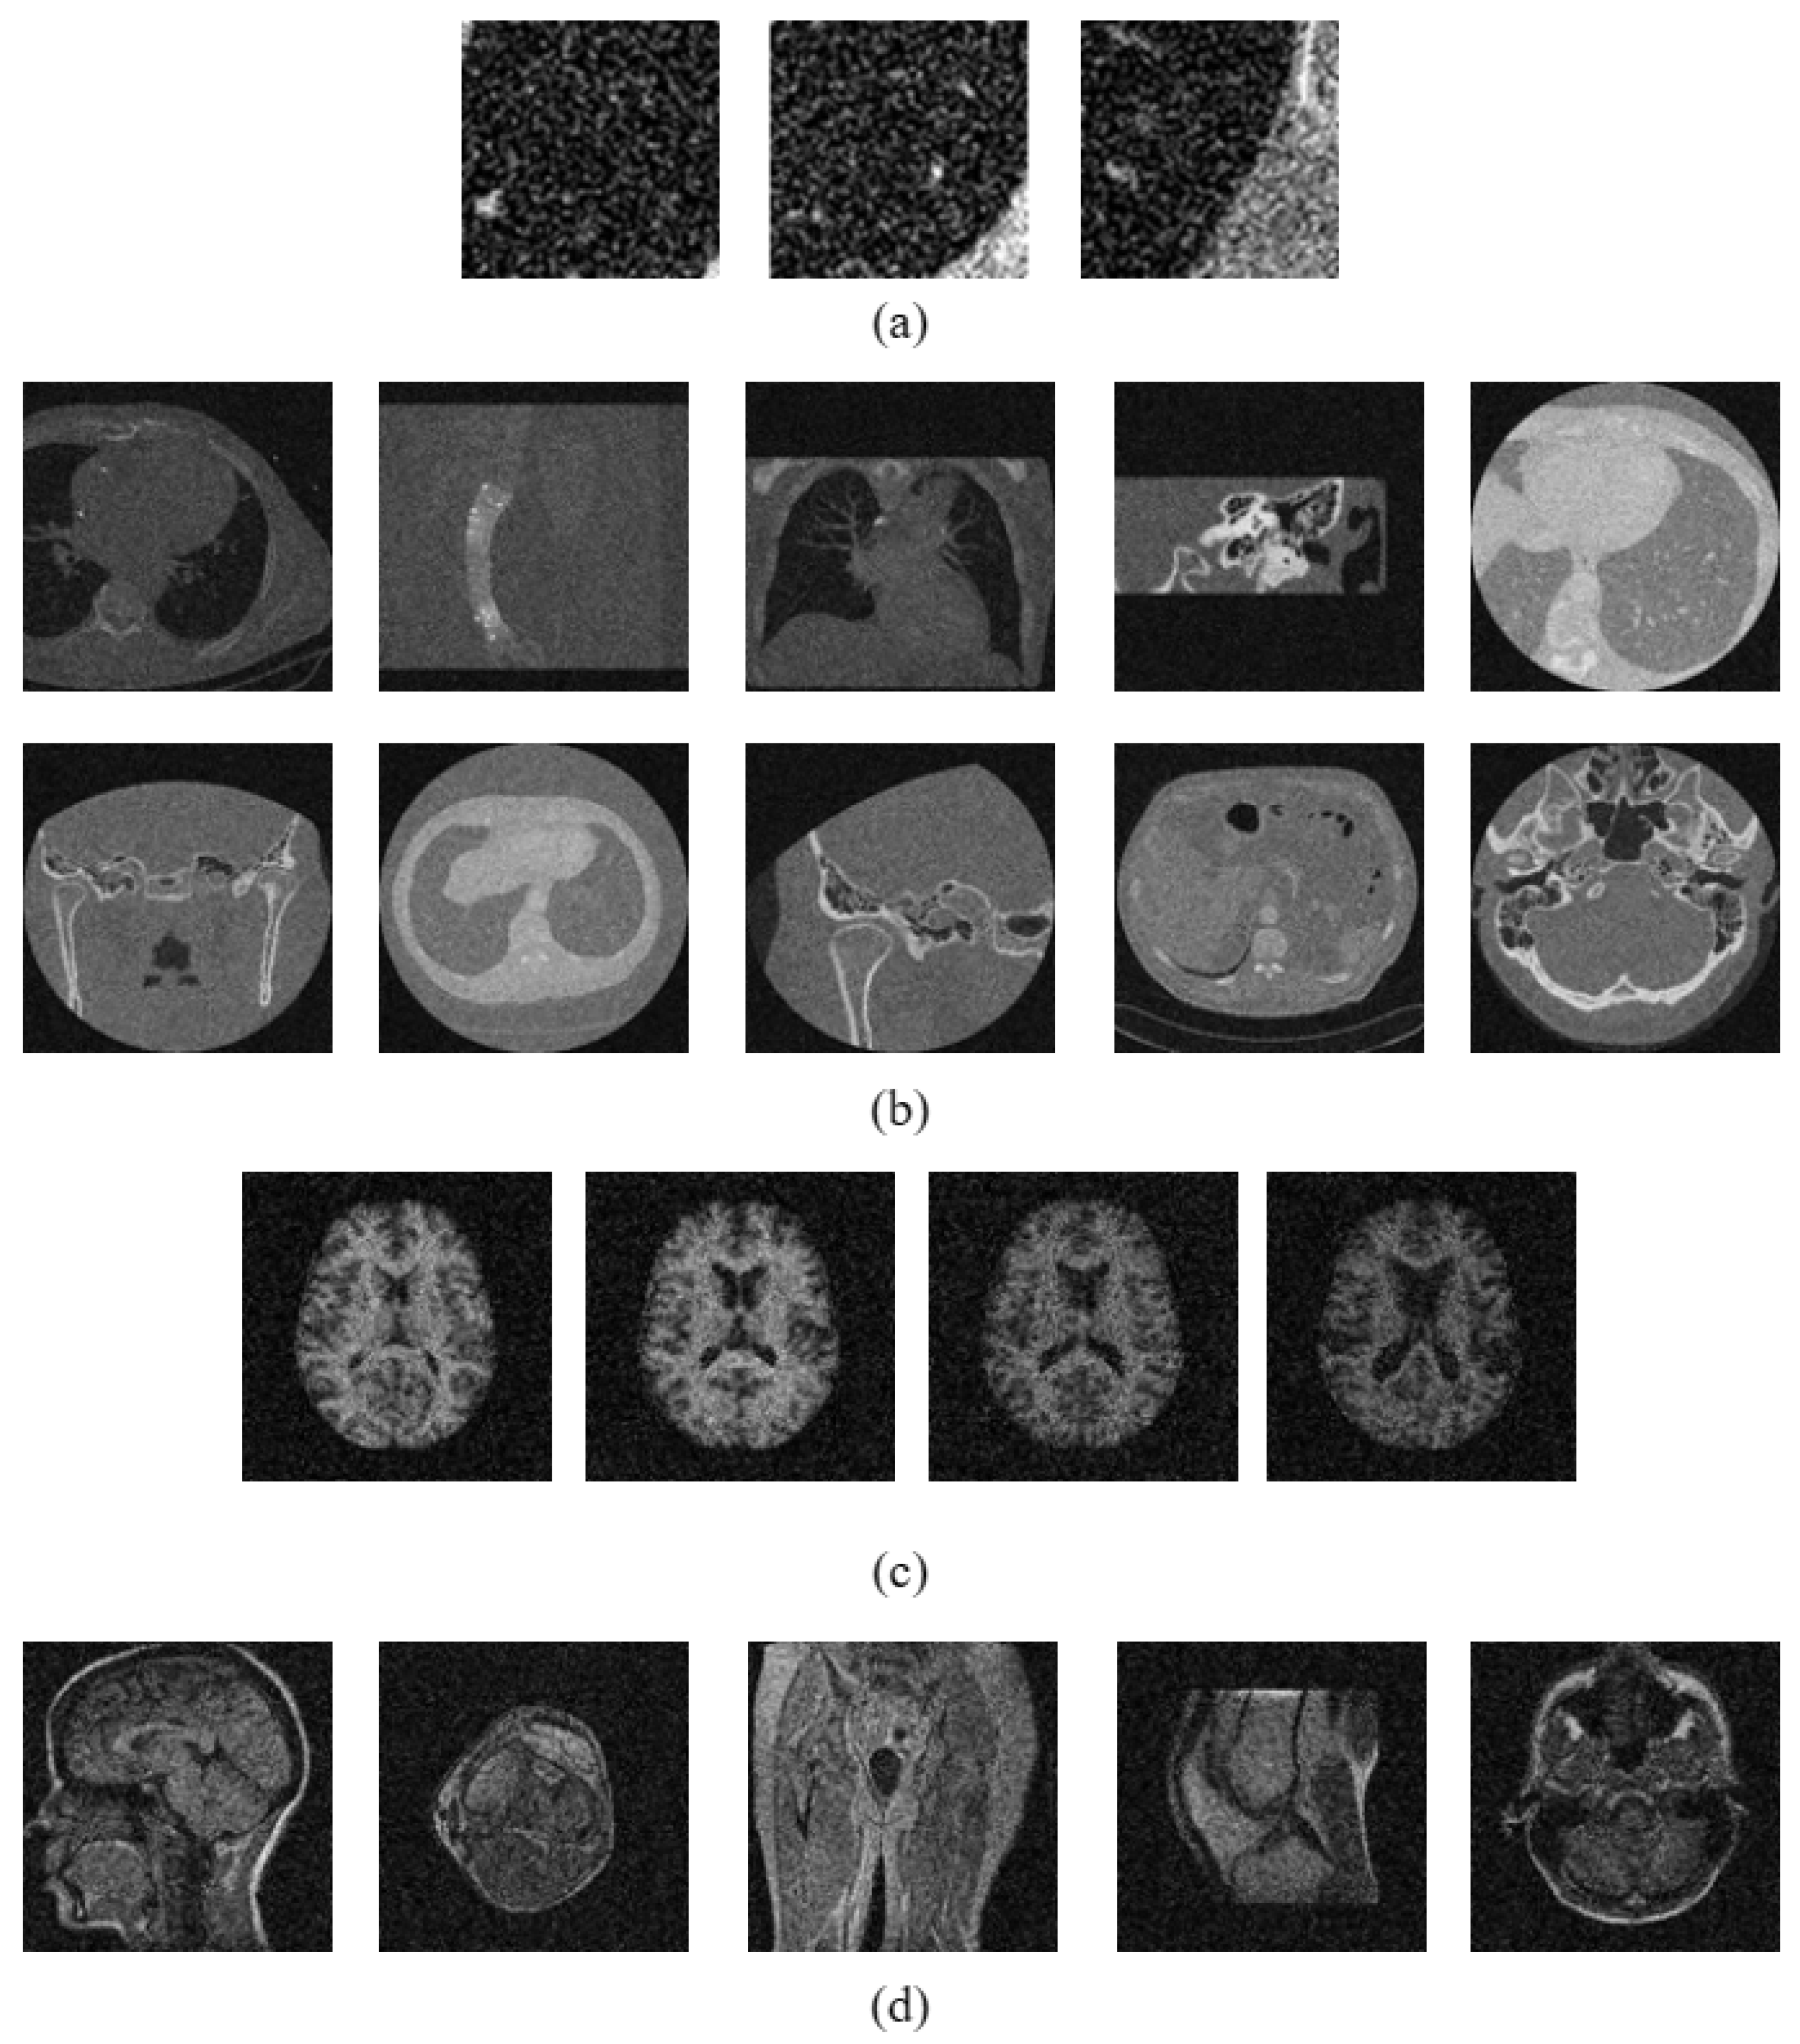

3.3. Dataset Description

- Emphysema-CT Database. Available online: http://image.diku.dk/emphysema_database/ (accessed on 15 December 2023).

- OASIS-MRI Database. Available online: http://www.oasis-brains.org/ (accessed on 15 December 2023).